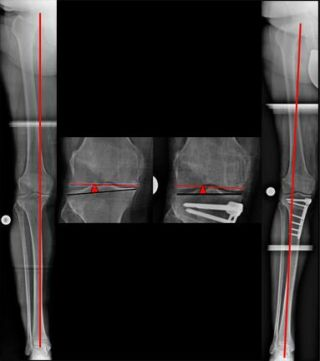

Zuklappende Osteotomie, kniegelenksnah, am Oberschenkel bei X-Bein (Bild 3).